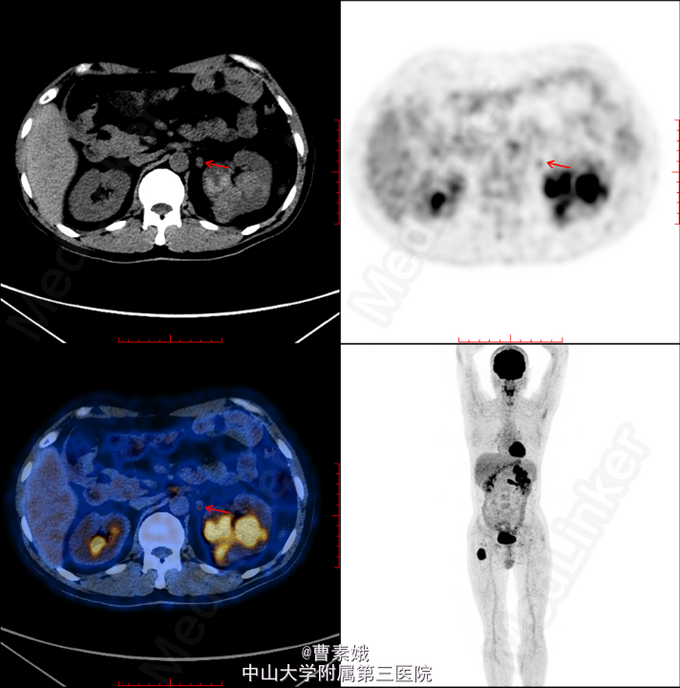

初步诊断:右股骨近端骨肿瘤(?)。 考虑右股骨肿物性质未明,遂于我院行全身PET/CT及腹部CT增强扫面,检查结果提示:1、左肾肿块并左肾静脉充盈缺损,代谢活跃,考虑左肾癌(透明细胞癌可能)并左肾静脉癌栓形成;双侧肾上腺座椅;腹膜后淋巴结转移;左侧股骨 经济股骨上段骨转移。随后患者行“左股骨肿物+左肾肿物穿刺活检术”,冰冻病理结果提示:左肾透明细胞癌,左股骨肿物考虑肾透明细胞癌转移。考虑患者肾透明细胞癌多发转移,无手术指征,转入肿瘤内科予索坦靶向治疗。